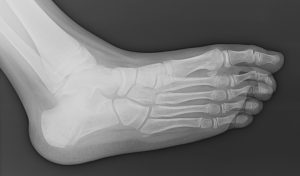

La diagnosi viene solitamente confermata con la radiografia del piede che deve essere eseguita in tre proiezioni: antero-posteriore, laterale in carico, obliqua a 45° (fondamentale per le sinostosi calcaneo-scafoidee) e la proiezione calcaneare di Harris (fondamentale per la sinostosi astragalo-calcaneare).